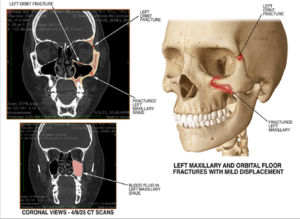

- Multiple fractured bones in her face, including left orbital and left maxillary fractures

Complicating her treatment, the young girl was bravely battling cancer that was affecting one of her eyes. Because of the risk of damaging her vision, doctors determined that surgically repairing certain facial fractures caused in the wreck was too dangerous. While she underwent femur and ankle surgeries, some facial fractures were left untreated surgically to preserve her eyesight.